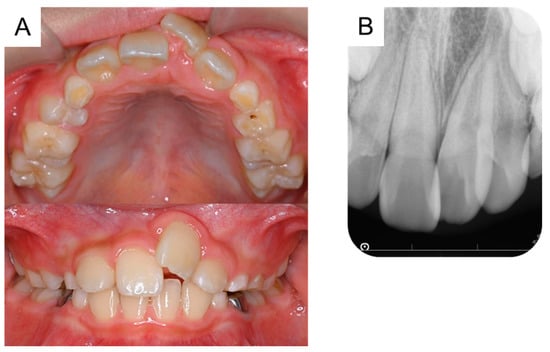

By the time the patient was aged 8 years and 2 months, the permanent maxillary left central incisor had not erupted in the oral cavity (Figure 3A). A periapical radiograph revealed the presence of a calcified tissue near the crown of the permanent maxillary left central incisor (Figure 3B). Considering the difference in the eruption time of the bilateral permanent maxillary central incisors, we decided to take an immediate surgical approach. One month later, we surgically removed the calcified tissue and the bone covering the permanent maxillary left central incisor under physical restraint. The extracted calcified tissue measured 5 mm × 5 mm (Figure 3C). Histopathological examination showed the presence of a tooth-like structure with enamel, dentin, pulp, and reduced enamel epithelium, confirming the diagnosis of a third supernumerary tooth (Figure 4).

Figure 3. Extraction of the third supernumerary tooth. (A) Intraoral photograph at the age of 8 years and 2 months. (B) Periapical radiograph showing the third supernumerary tooth at the age of 8 years and 2 months. (C) Extracted calcified tissue, which was later diagnosed as the third supernumerary tooth. Scale bar: 5 mm.